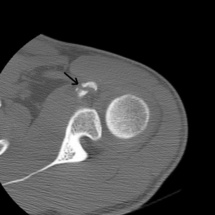

C'est en inspectant la région antérieure de l'épaule qu'a été constatée une interruption de la corticale osseuse sur le segment horizontal de la coracoïde.

Cette anomalie a été confirmé sur 2 coupes distinctes.